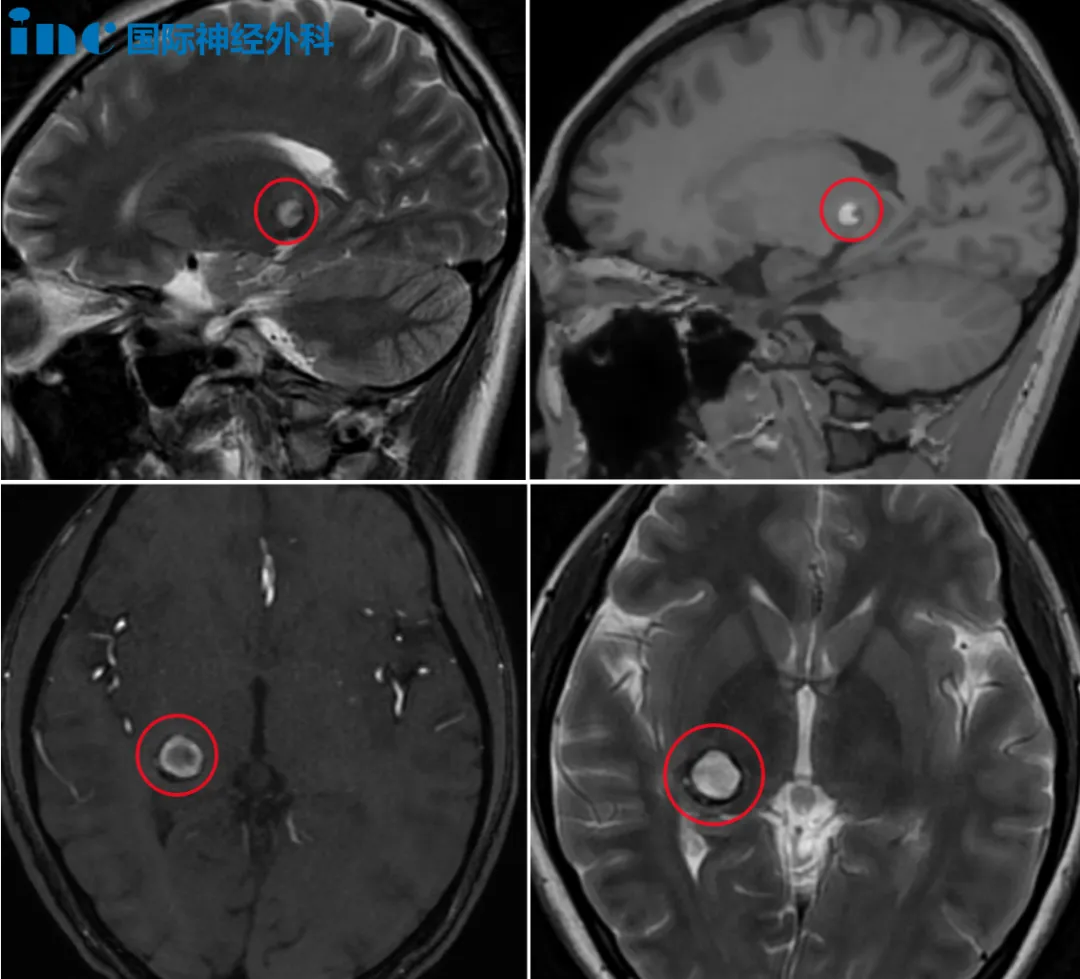

2024年5月,20岁的小雨被确诊为右侧丘脑海绵状血管瘤少量出血。2024年6月7日,巴教授为小雨成功进行示范手术,手术非常顺利、完全切除病灶。从5月16日出现症状到成功手术,不到一个月时间,小雨脑袋里的“不定时炸弹”得到成功拆除,早已恢复正常的学习生活!

巴教授评估了小雨2024年6月6日手术前、6月8日手术后,以及10月份最新的核磁。最新的复查MRI上显示病灶被完全切除,结果很好。教授认为目前的学业对她不会有影响,生活中没有需要特别注意的。

视野被限制,焦点之外的一切也都变得朦胧不清。紧接着,头痛如影随形。小雨和家人到当地医院进行CT检查发现脑出血,立即入院,头颅核磁报告右侧丘脑见异常信号灶,考虑海绵状血管瘤少量出血。